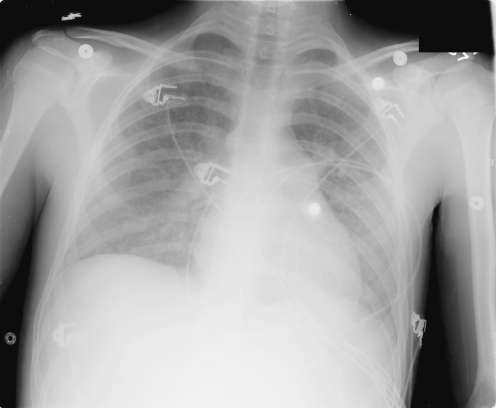

Upon arrival in our emergency department, the patient appeared jaundiced and in moderate distress, complaining of right upper quadrant abdominal pain. Vital signs were remarkable for a maximal temperature of 38.0° C and a sinus tachycardia at 103 beats/min. Review of systems was positive for nausea. On physical exam, the medial aspect of the left proximal upper extremity was exquisitely tender to palpation from the elbow to the mid-axilla. The right upper quadrant and epigastrium were moderately tender to palpation without guarding or rigidity, and the liver edge was palpable 3 cm below the costal margin. Laboratory values were remarkable for a WBC of 5.2×109/l with 92% neutrophils, platelet count of 73×109/l, ALT 126 IU/l, AST 133 IU/l, total bilirubin 8.0 mg/dl, and direct bilirubin 5.4 mg/dl. Duplex ultrasound of the left upper extremity revealed occlusive thrombus in the cephalic vein extending from just above the antecubital fossa to the origin of the subclavian vein. Abdominal ultrasound confirmed the suspected hepatosplenomegaly. Chest radiography demonstrated focal infiltrates in the left lung (Fig. 1). Heparin was initially withheld due to the low platelet count and superficial location of the thrombus, and the patient was admitted to the general pediatric ward.

Fig. 1.

AP CXR showing mild diffuse bilateral pulmonary infiltrates. 566×465 mm (96×96 DPI)